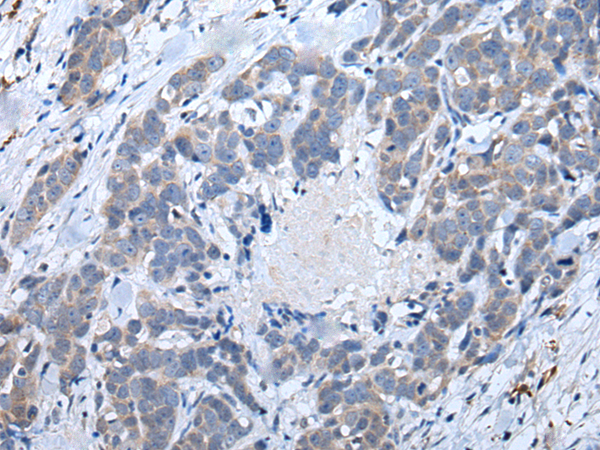

IHC positive control: |

Human ovarian cancer and human thyroid cancer |

IHC Recommend dilution: |

40-200 |